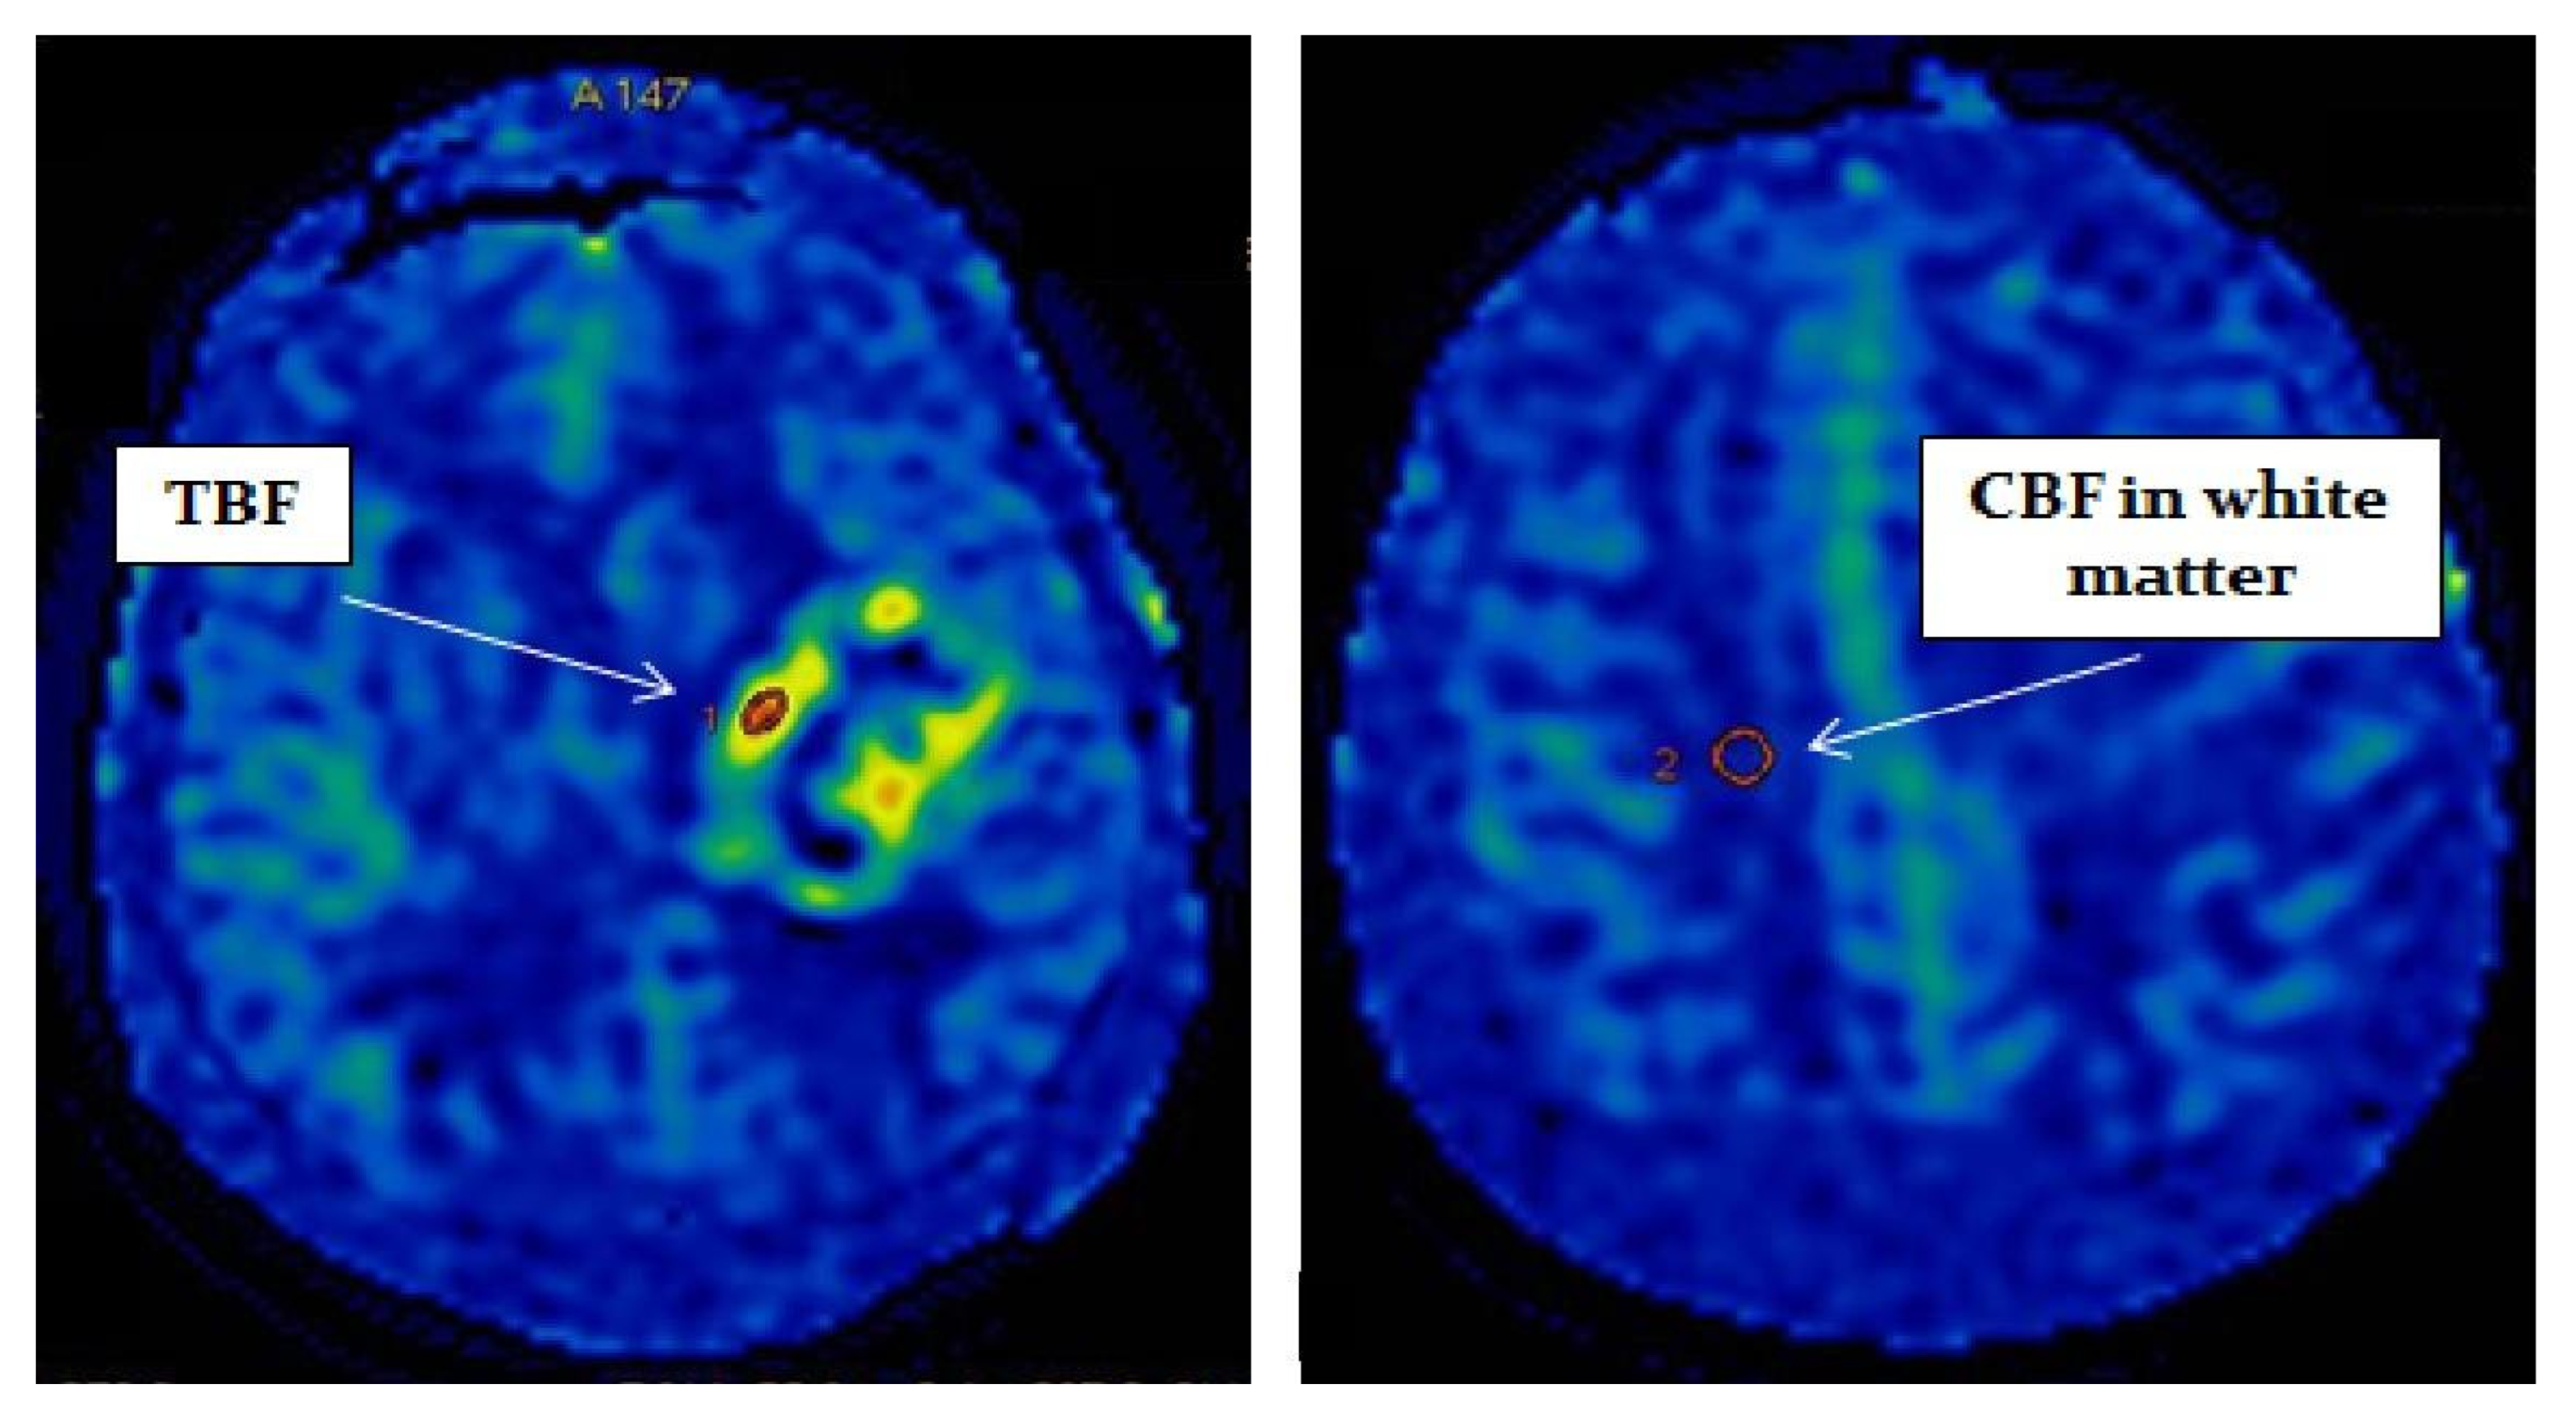

In all cases, blood flow maps were fused with anatomical images (T2, T2-FLAIR, enhanced T1) using the NeuroRegistration program (GE Healthcare)—Figure 2.

Figure 2.

MRI scans and quantitative CBF maps of anterofrontal region IDH1-wildtype glioblastoma. ASL perfusion showed high TBF values (247.2 mL/100 g/min).